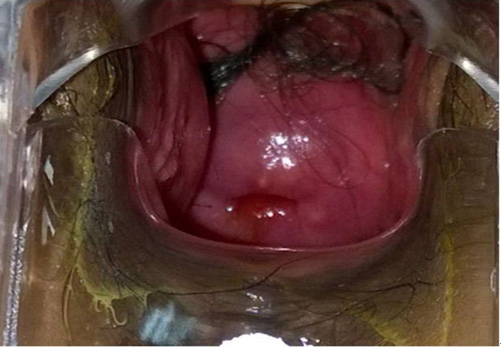

医疗范围:宫颈癌、卵巢癌、子宫内膜癌、外阴癌、阴道癌及恶性葡萄胎和绒癌等各种恶性肿瘤的手术、化疗及综合治疗。

全子宫加双侧附件切除加腹膜后畸胎瘤切除术